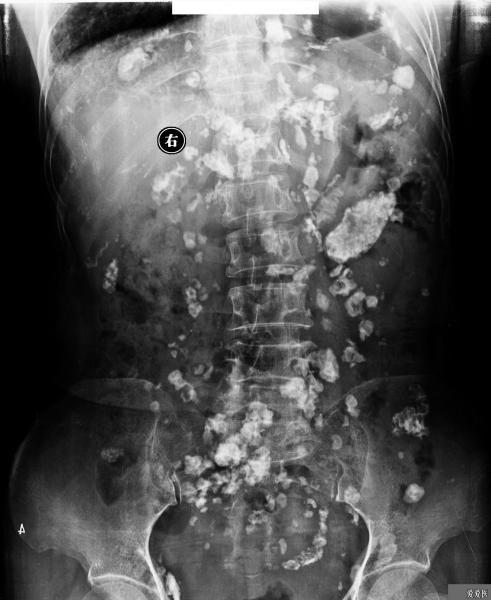

本帖最后由 274005 于 2011-3-18 15:14 编辑 患者是因为腰痛入院检查腰椎,检查前并没有服用过造影剂!

该患者摄腰椎正侧位后,发现腹腔非常罕见的广泛的钙化,而且双侧肋膈角变钝,左侧膈肌感觉明显向上有牵拉,左侧胸廓有塌陷。